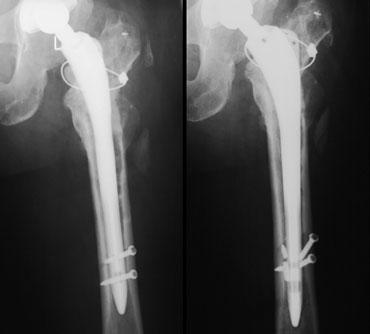

Gãy xương quanh khớp nhân tạo

Gãy xương có thể xảy ra sau phẫu thuật ở những bệnh nhân có chất lượng xương kém và sử dụng khớp nhân tạo thay thế có cán dài, hoặc khi giải phẫu bất thường như trong trường hợp loạn sản khớp háng hoặc đã từng phẫu thuật trước đó.

Gãy xương cũng phổ biến hơn với các cán xương đùi không xi măng, vì các loại này phải vừa khít chính xác và có thể gây gãy xương trong quá trình đặt khớp.

Tỷ lệ gãy xương dao động từ 0,1 đến 1,0 phần trăm đối với các thành phần có xi măng và từ 3 đến 18 phần trăm đối với các thành phần không xi măng. Hầu hết các trường hợp gãy xương trong phẫu thuật xảy ra ở phía xương đùi.

Fractures

Tỷ lệ mắc sau phẫu thuật:

– THA có xi măng: 0,4%

– Khớp giả ép khít: 2,5%

– Phẫu thuật thay khớp háng lại: 7,2%

Thông thường không ảnh hưởng đến kết quả, nhưng có thể cần dùng cáp vòng cerclage.

Đôi khi phẫu thuật viên tạo một lỗ kiểm soát có chủ ý trong quá trình phẫu thuật lại để hỗ trợ tháo bỏ thành phần xương đùi đã được đặt trước đó.

Gãy xương trong quá trình theo dõi là hậu quả của tình trạng lỏng khớp, bệnh lý do hạt vi thể, nhiễm trùng hoặc các trường hợp nặng của hiện tượng che chắn ứng suất.